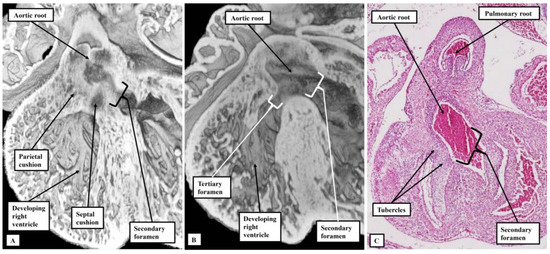

3.1. Evidence from Development